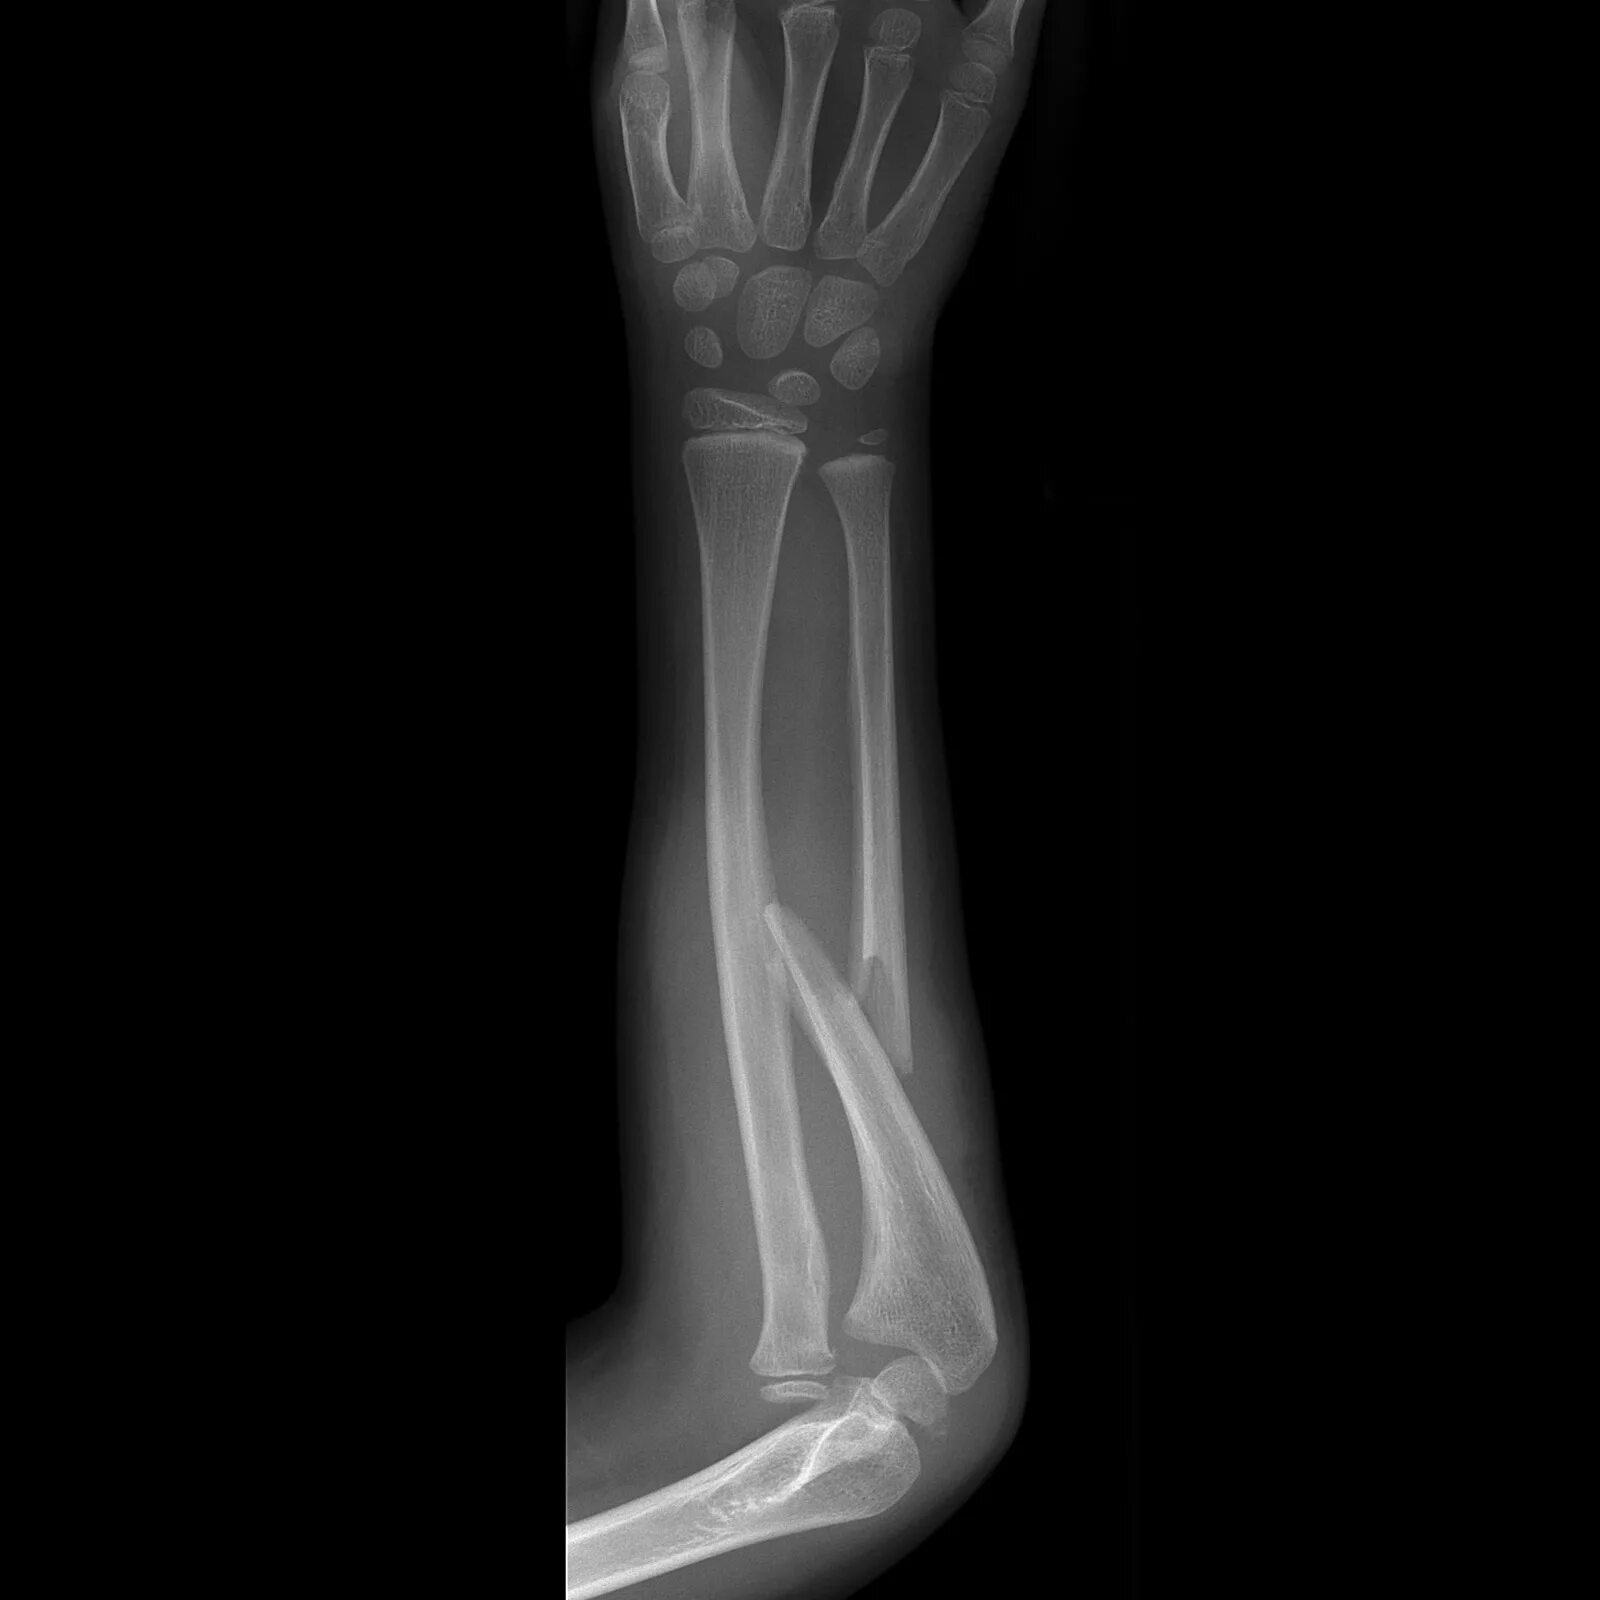

Fracture modeling